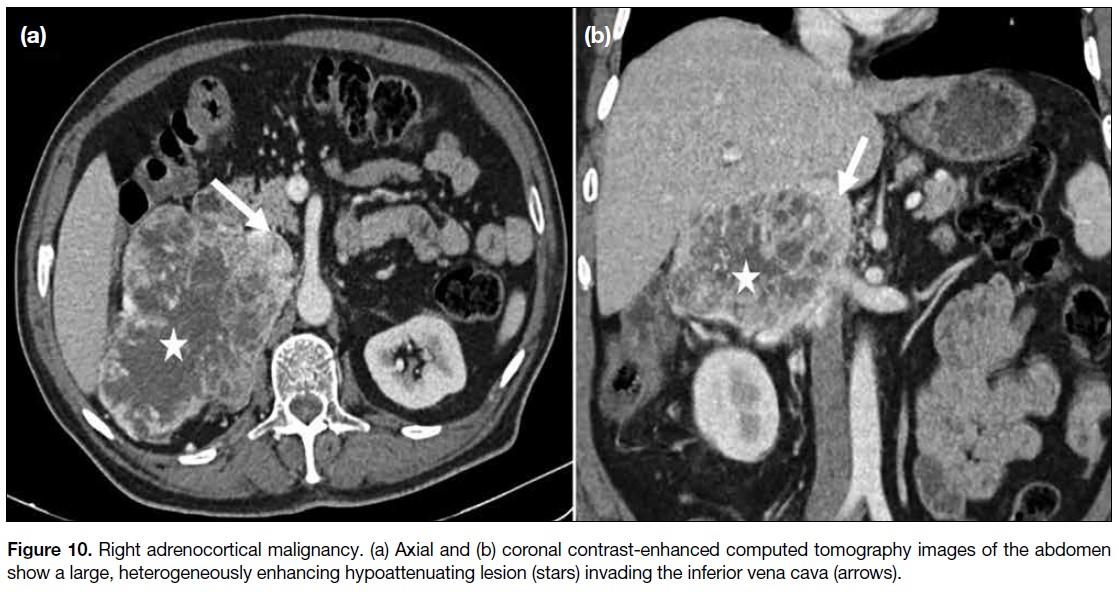

ACQUIRED PATHOLOGIES

The major acquired venous pathologies in abdominopelvic

malignancies include external compression or infiltration

of the IVC and its draining veins by neoplasms (Figures 10 and 11), metastatic lymph nodes (Figure 12), and/or

intraluminal thrombosis.

Figure 10. Right adrenocortical malignancy. (a) Axial and (b) coronal contrast-enhanced computed tomography images of the abdomen

show a large, heterogeneously enhancing hypoattenuating lesion (stars) invading the inferior vena cava (arrows).